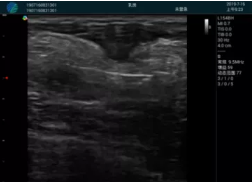

清晰顯示孕囊,通過(guò)軟件包計算孕齡7w+6d

M20實(shí)時(shí)引導,術(shù)中清晰顯示孕囊被破壞和抽吸針的過(guò)程,清晰顯示吸引針

抽吸結束后縱切子宮,孕囊已被完全抽吸,未見(jiàn)明顯殘留

橫切子宮,發(fā)現右側宮腔靠近宮角處有少許脫模樣殘留

M20引導下,抽吸針找到右側宮角處再次清掃

二次抽吸后再次進(jìn)行超聲檢查,宮腔未見(jiàn)殘留,宮腔線(xiàn)清晰顯示